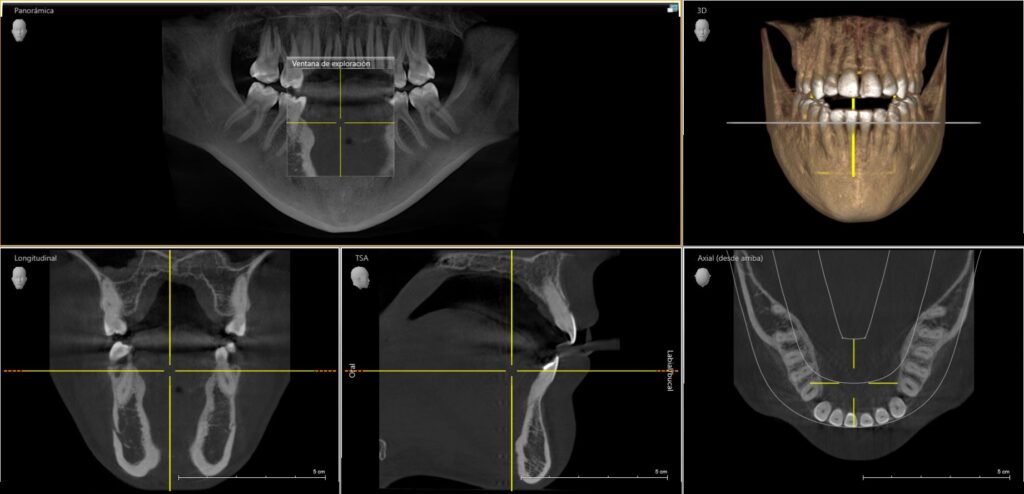

El caso clínico de nuestra paciente presentó inicialmente una mordida abierta anterior moderada causada principalmente por una deglución atípica. Esta condición provoca que la lengua presione incorrectamente contra los dientes, lo que deriva en un desplazamiento gradual de la dentición, incluso con la utilización de retenedores fijos postratamiento.

Además, el diagnóstico reveló ausencia de la pieza dental 26 y rotación mesial del diente 27, junto con segundos molares superiores mesiorrotados, ausencia del diente 46 (que requirió implante) y una sonrisa baja que no mostraba encía, influyendo negativamente en la estética facial.

A pesar del uso de retenedores fijos, la paciente experimentó una recidiva debido a la persistencia de la deglución atípica. Esta condición muscular desfavorable hizo que se volvieran a mover ligeramente algunos dientes, comprometiendo parcialmente los resultados iniciales del tratamiento con brackets.

Una vez asegurada la posición correcta de la lengua mediante la intervención logopédica, se procedió con el retratamiento de ortodoncia utilizando alineadores transparentes.

Los alineadores transparentes ofrecieron varias ventajas: comodidad, estética y facilidad para mantener una buena higiene bucal durante el tratamiento. Además, permitieron ajustes precisos y progresivos para corregir la ligera recidiva dental de manera efectiva.